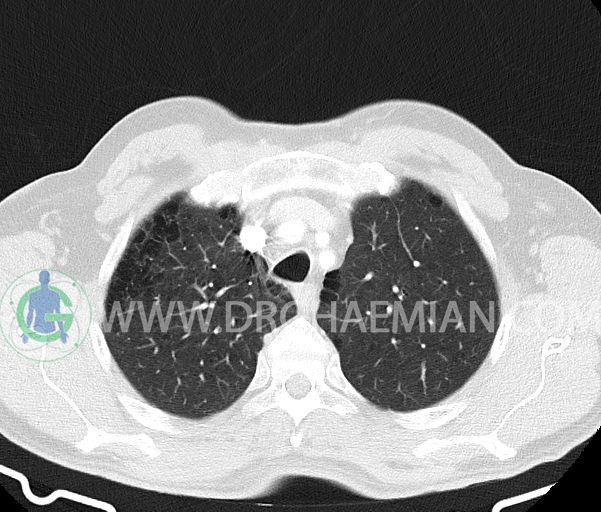

در سی تی اسکن اسپیرال ریه و مدیاستن- شکم و لگن با و بدون کنتراست خوراکی و وریدی (مولتی دیدکتور 16 با مقاطع ظریف و بازسازی های ساژیتال و کرونال) :

– آمفیزم سنتری لوبولار در لوب فوقانی هر دو سمت با ارجحیت در سمت راست

–آمفیزم پاراسپتال در هر دو ریه

–توده هایپودنس به سایز 10x7mm در ساب کپسولار سگمان 8کبد با Enhancement هوموژن با نمای Blood pool match مطرح کننده همانژیوم کبدی

–سنگ به سایز 3mm در کالیس میانی کلیه چپ

– کیست کورتیکال در هر دو کلیه به حداکثر سایز 19mm در سمت چپ و 7mm در سمت راست (Bosniack 1)